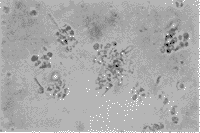

细胞培养3~5天后,细胞贴壁,体积小,圆形,分散存在,部分细胞有轴突伸展(照片1)。微波辐照后,Ⅰ组细胞发生聚集,仍可见轴突,细胞边界清楚(照片2);Ⅱ组细胞聚集成团,少数细胞散在,轴突消失,边缘较模糊(照片3),偶见“环状”细胞出现(照片4);Ⅲ组细胞与Ⅱ组相似,散在细胞较多;Ⅳ组细胞多数边界模糊,部分细胞漂浮,可见细胞碎片(照片5)。辐照后细胞继续培养48小时后,Ⅰ组细胞大部分散在,少量聚集(照片6),Ⅱ组细胞仍聚集成团,但细胞亮,边缘清楚,Ⅲ组变化不明显,Ⅳ组细胞减少,杂质多。

1 正常RGC形态(×250)

2 10mW/cm2(30min)辐照后细胞形态(×250)

3 10mW/cm2(60min)辐照后细胞形态(×250)

4 10mW/cm2(60min)辐照后凋亡样细胞(×400)

5 30mW/cm2(60min)辐照后细胞破坏较重(×250)

6 辐照后再培养48h的细胞形态(×250)

附图 微波辐照及再培养对细胞形态的影响